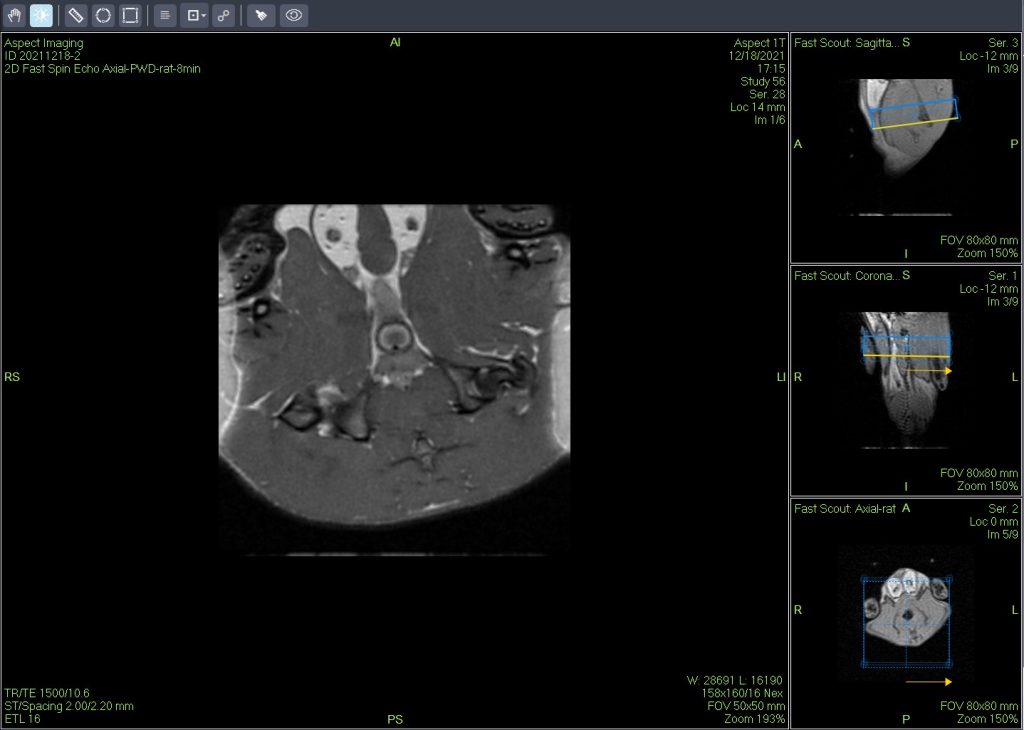

小鼠皮下肿瘤MRI造影成像效果与造影剂代谢过程研究。

使用仪器: 小动物核磁共振成像仪NM20-060H-I 其他相关应用: 核磁共振造影剂弛豫率分析造影剂分析案例 核磁共振成像与分析技术在生命科学领域应用解决方案